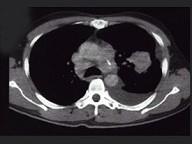

问题 女,68岁,咳嗽伴胸痛胸闷1个月,CT检查如图,最可能的诊断为 ( )

选项 A.左上肺不张 B.左上肺周围型肺癌伴胸膜转移 C.左上肺血管瘤 D.左上肺软骨肉瘤伴胸膜转移 E.左上肺结核

答案 B